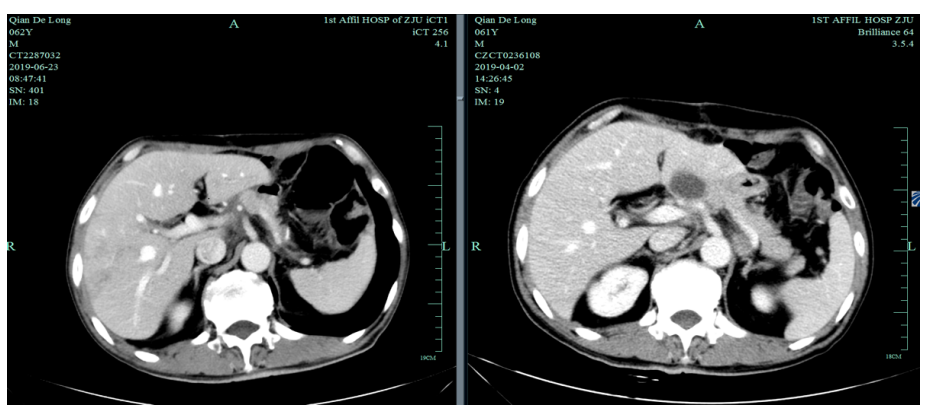

入我院后全面进行评估(2019.4):全腹部CT平扫+增强评估提示腹膜后,胰腺周围多发淋巴结增大,淋巴结转移考虑。

2019-4-2至2019-6-5行SOX+赫赛汀 q3w 4周期联合化疗:具体为奥沙利铂220mgD1、替吉奥3# BID D1-14、赫赛汀400mg(首次)+300mg。

一线化疗疗效评估(2019.6 vs 2019.4):胃癌术后改变。影像评估CR。